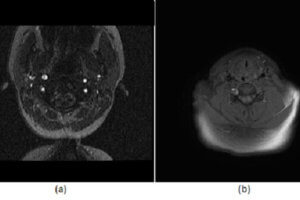

Carotid Artery Dissection, MRA

Carotid/vertebral artery dissection is an underdiagnosed disease that can result in substantial morbidity. It has an incidence of 1-1.5/100000 and disproportionately affects young patients. Diagnosis is challenging clinically because the symptoms are... Read more »